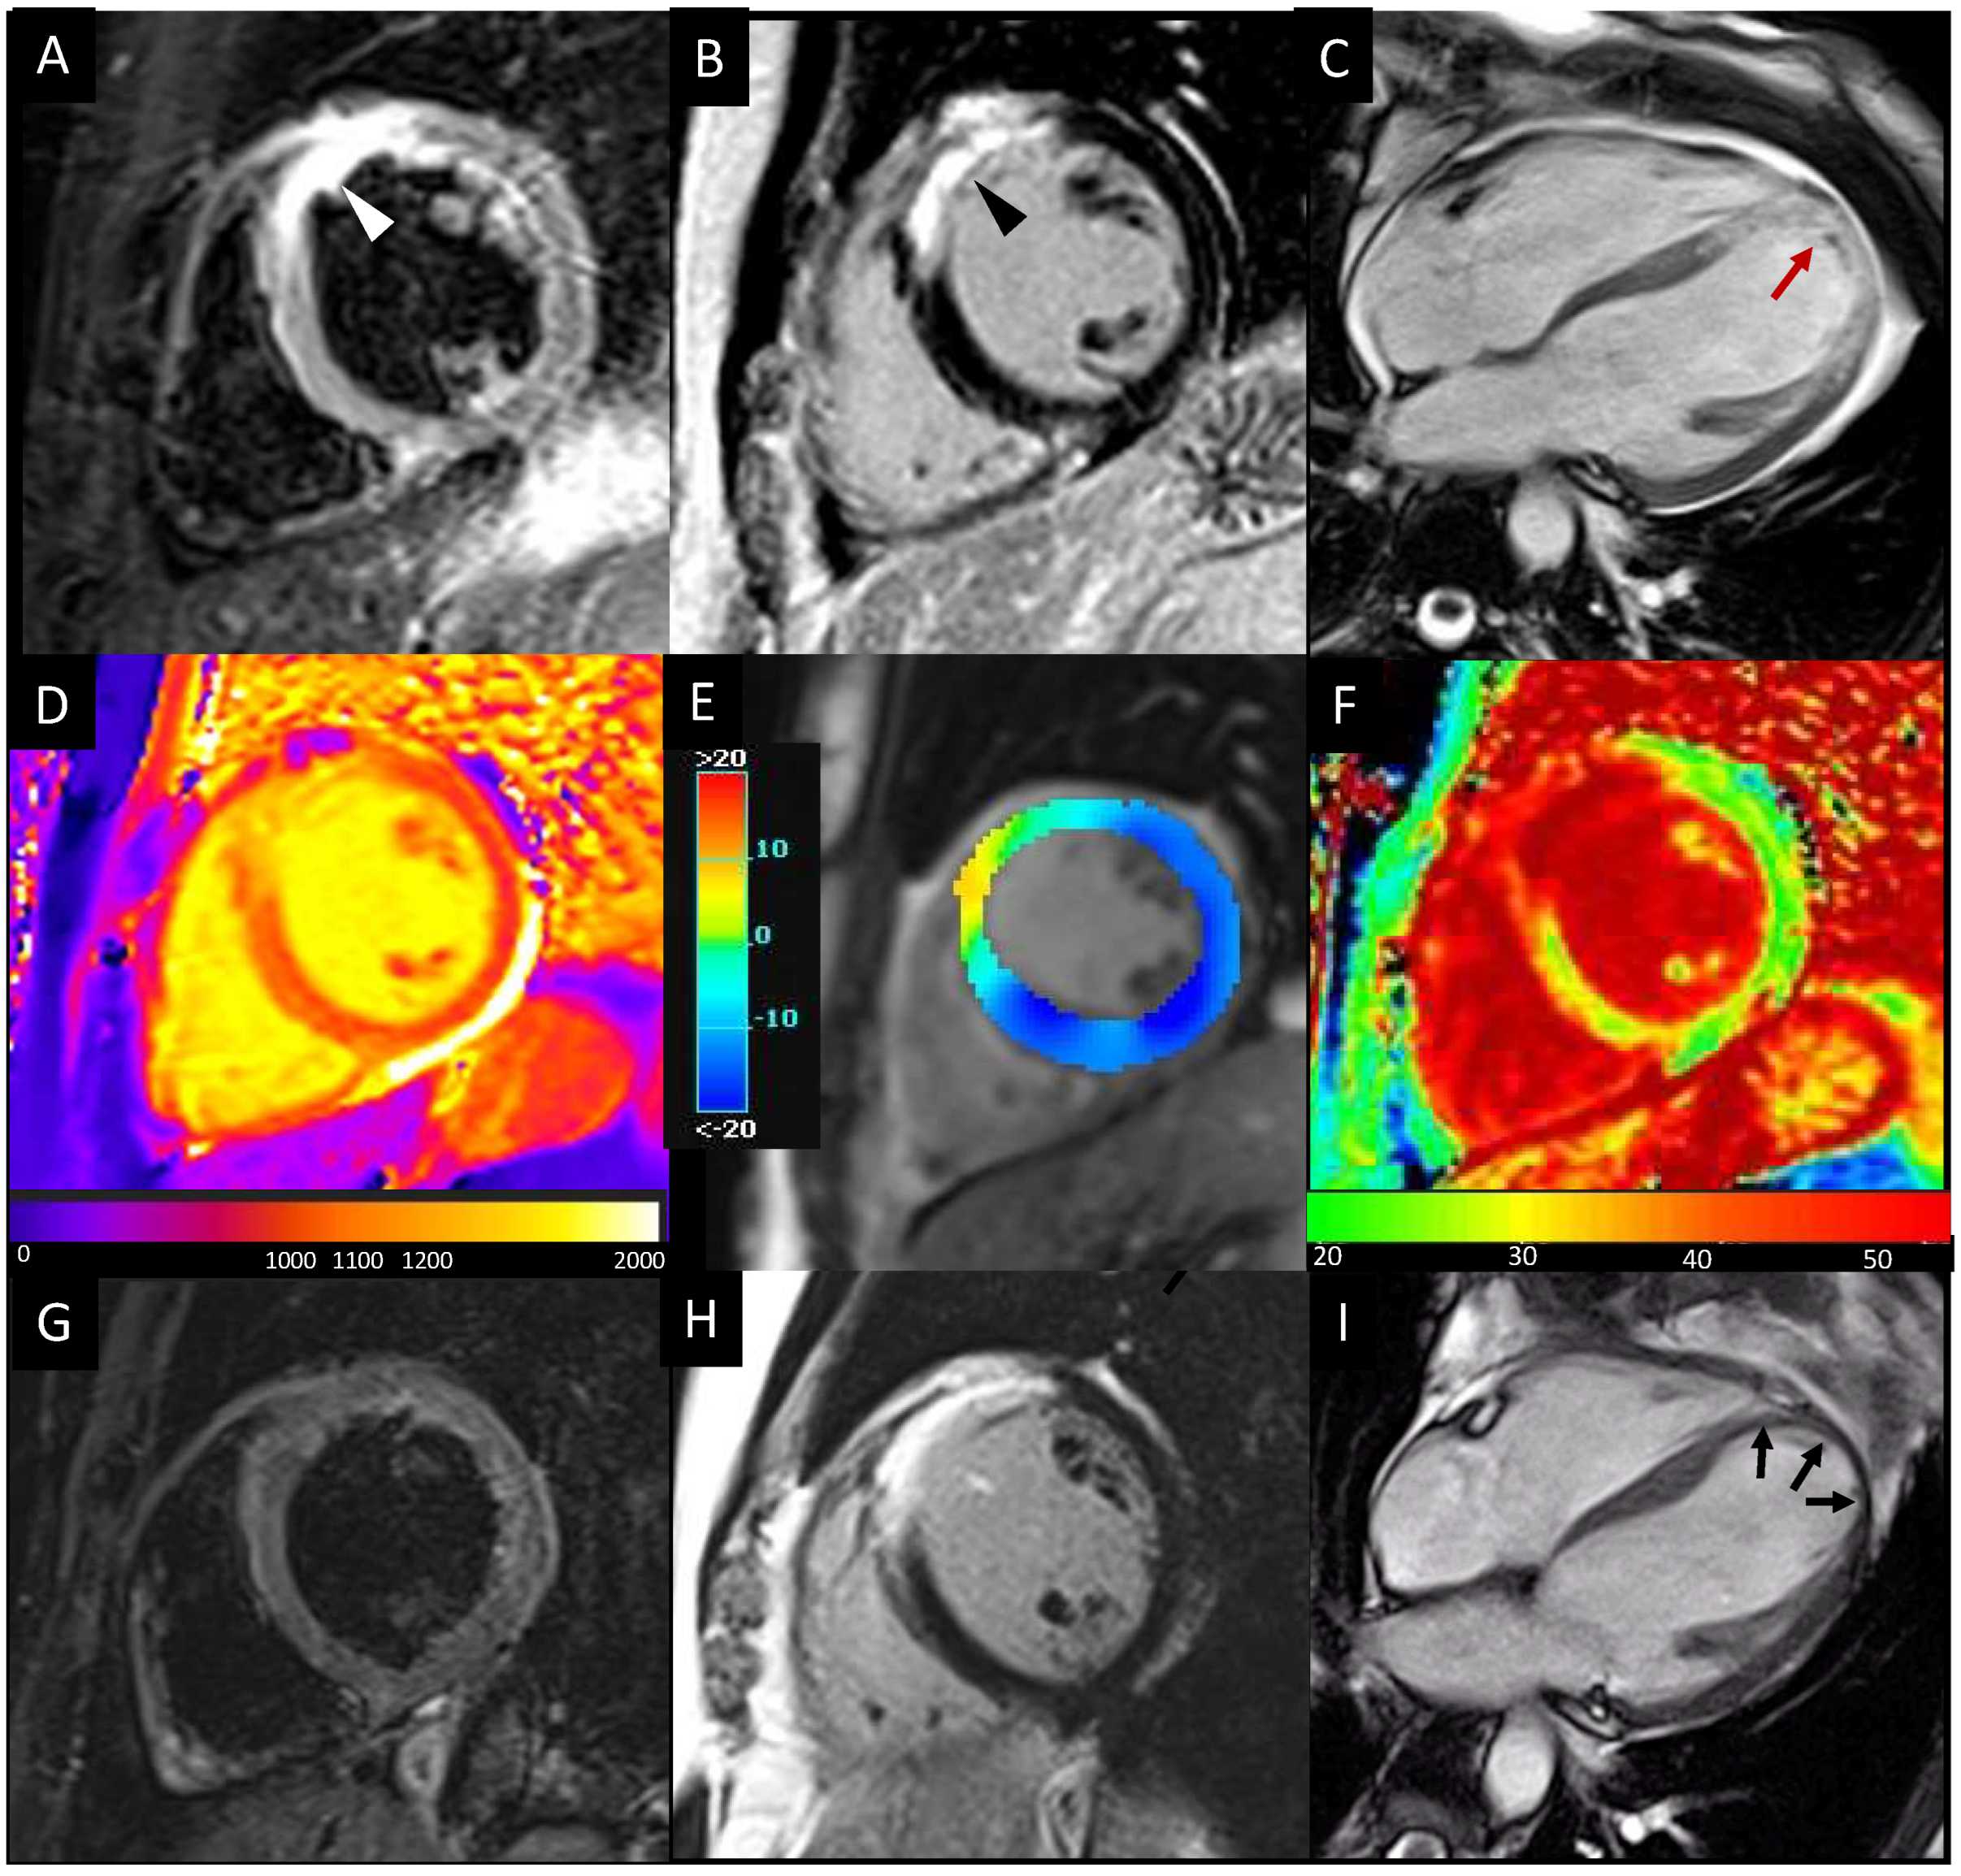

3. Myocardial Strain Analysis

4. Tissue Characterization

4.1. LGE, MVO, and IMH

4.2. T1/T2/ECV Mapping